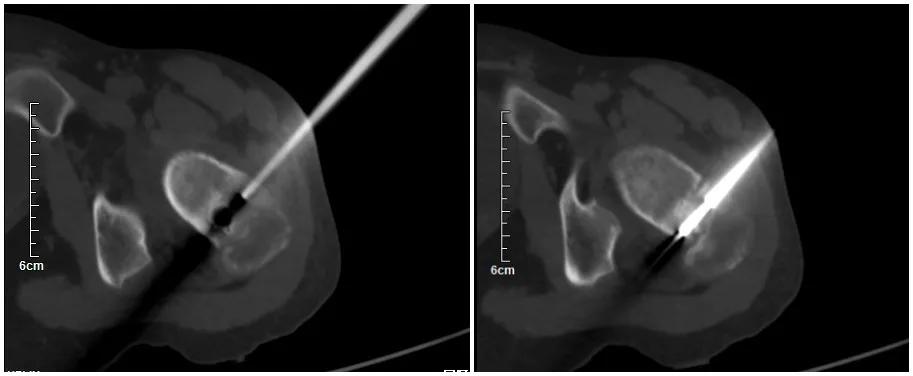

由于邓某某年龄较小,骨骺未愈合,手术难度大,如若进行切开手术治疗,手术创伤较大,还不一定能找到肿瘤。同时,邓某某左侧股骨颈肿瘤位置距离骨骺线较近,若不能精准定位,极易破坏骨骺线,导致患肢停止生长。对于肿瘤侵犯左侧股骨颈,肿瘤继续生长危害极大,肿瘤切除仍然是治疗的关键。考虑到患者的实际情况,与家属沟通后,在华西段宏教授指导下我科为患者成功进行了国内首例AR辅助股骨颈肿瘤精准治疗手术。

AR技术是把患者医学影像重建后的虚拟模型与真实世界相融合,运用光学显示技术、人机交互技术、位置坐标跟踪、标定、注册等前沿科学技术,为使用者提供一个全方位、多角度、沉浸式、可交互的操作体验。并且可以将虚拟信息与现实场景信息进行对位匹配,在手术中可以精准定位病灶位置,为医生提供更轻松、迅速和安全地手术辅助形式,对患者来说,可以大大减小手术对患者的伤害。

医生和病人都知道,在手术中,精度非常重要。而现在,AR可以帮助外科医生提高手术的效率。无论是进行微创手术,还是定位骨与软组织肿瘤,AR医疗技术都可以帮助医生挽救生命,为患者提供无缝治疗。